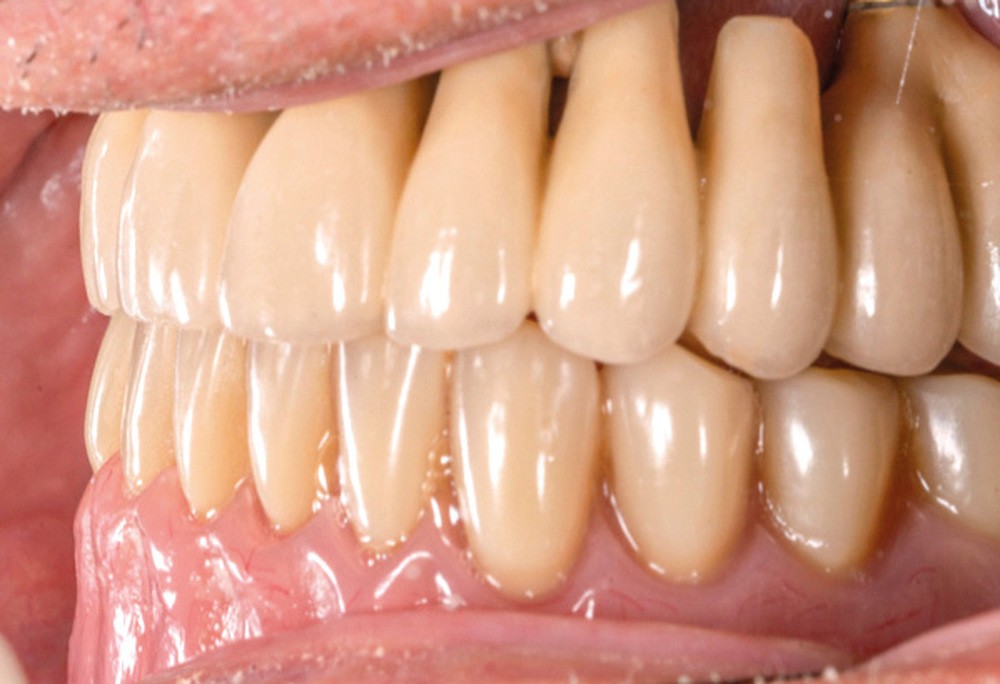

La détermination d’un positionnement correct du maxillaire dans le massif cranio-facial est essentielle lors d’une réhabilitation prothétique étendue. Plans et lignes de références permettent de transférer la position du maxillaire sur articulateur et d’évaluer l’agencement dentaire avec l’harmonie globale du visage [1]. La conception et la réalisation d’une prothèse complète, amovible ou transvissée, sont des exercices difficiles pour le praticien, comme pour le prothésiste de laboratoire, qui doivent imaginer et recréer de manière optimale les fonctions et l’esthétique perdues [2].

En prothèse amovible complète, le plan d’occlusion correspond au plan selon lequel seront montées les dents prothétiques. En règle générale, il passe par le bord libre des deux incisives centrales et le bord distal des deuxièmes molaires inférieures [2]. Outre des répercussions d’ordre esthétique, un plan d’occlusion erroné peut perturber la cinématique mandibulaire, générer un inconfort, une impotence, voire un handicap fonctionnel. Des conséquences pathologiques à long terme telles que des myoarthropathies de l’appareil manducateur peuvent aussi se manifester [2].

Chez l’édenté total, la bonne orientation du plan d’occlusion prothétique permet de répondre à des impératifs fonctionnels et esthétiques :

L’orientation du plan d’occlusion est primordiale, car elle influe sur la puissance masticatoire du patient [3]. De plus, celui-ci assure également la stabilité des prothèses lors de la mastication. Un plan d’occlusion erroné peut créer une certaine instabilité et une inefficacité…